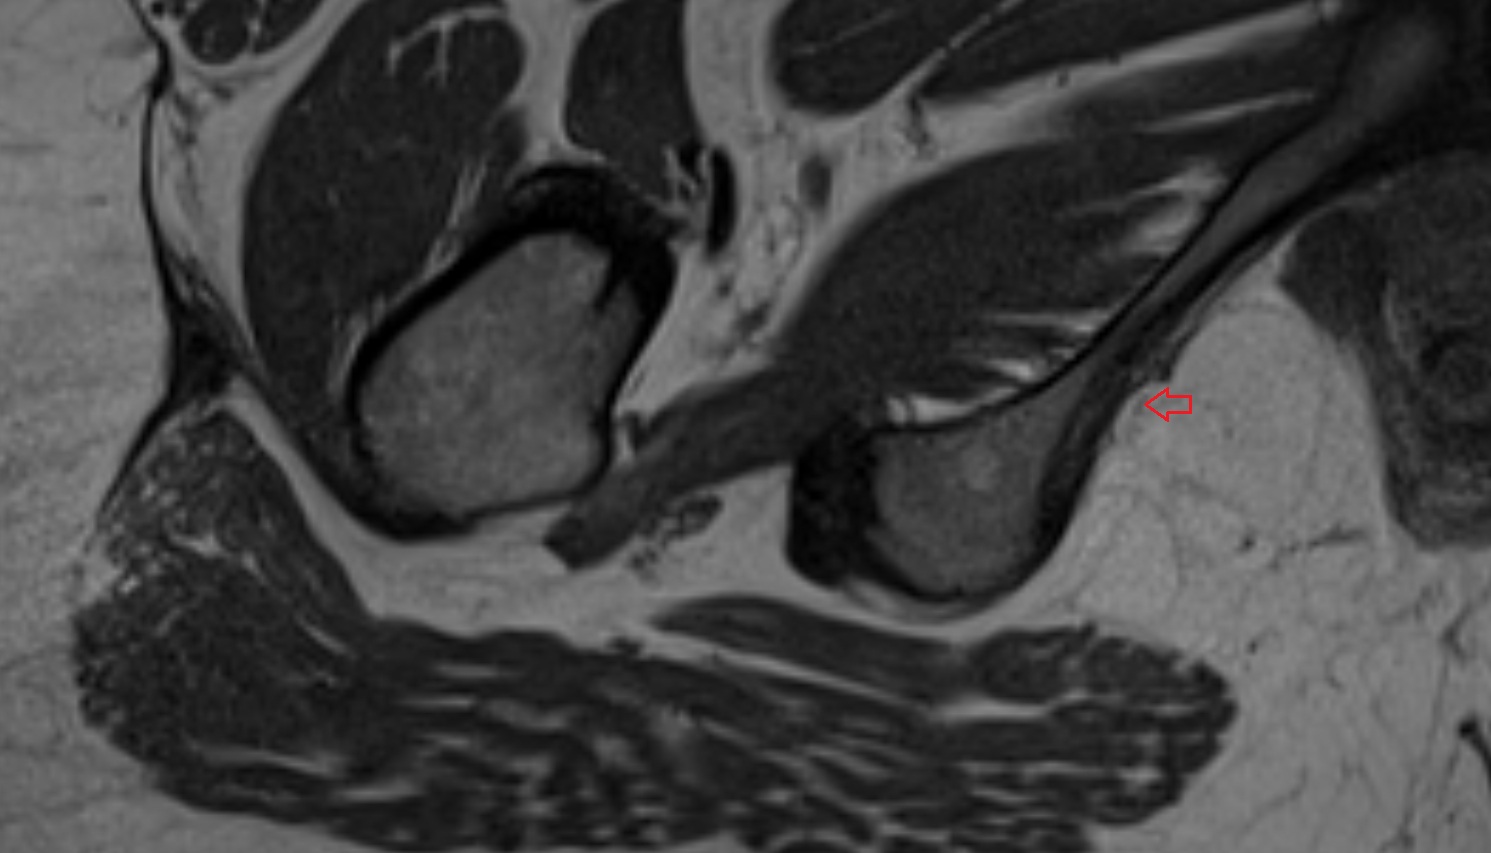

- Hip joint

- Head of femur

- Neck of femur

- Acetabular labrum

- Articular capsule of hip joint

- Iliofemoral Ligament superior band (transverse band, lateral band)

- Iliofemoral Ligament inferior band (vertical band, medial band)

- Ischiofemoral ligament

- Transverse acetabular ligament